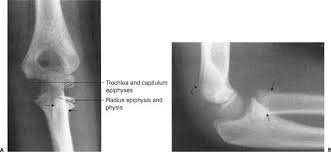

Think of the epiphyseal line as a permanent mark that tells us the bone has finished growing. You can see this line on an X-ray, and it’s helpful for doctors to determine bone age, which is particularly important for evaluating growth and development in children and adolescents.

The presence of an epiphyseal line on an x-ray indicates that the bone has finished growing in length.

Epiphyseal plates are growth plates that are found at the ends of long bones. These plates are made of cartilage and allow bones to grow in length. As a person gets older, these plates start to ossify (turn into bone). This process is called epiphyseal closure.

When epiphyseal closure is complete, a line appears on the x-ray where the epiphyseal plate used to be. This line is called the epiphyseal line.

* When the epiphyseal plates are closed, the epiphyseal line appears on an x-ray.

The epiphyseal line is a good indication that bone growth in length has stopped. Epiphyseal closure happens at different times for different bones and people. It’s usually complete by the end of puberty, around age 18 for females and 20 for males.

Here’s the thing: we can’t actually see the growth plates directly. They’re inside the bone. But, we can use X-rays to see the epiphyseal line, which is like a ghost of the growth plate once it’s closed.

The epiphyseal line will show up as a thin, dense line on the X-ray. It’s not super obvious, but an experienced doctor or radiologist can spot it.

Injury and Repair: Sometimes, injuries can affect the growth plates. For example, a fracture that crosses a growth plate could cause growth problems. The epiphyseal line helps doctors understand if the injury is affecting growth.